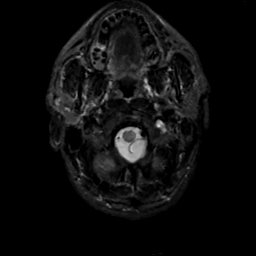

MR Study #14, June 2, 1991 -- Slice #2